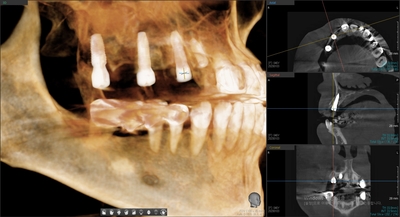

이 3D스캔과 CT를 바탕으로 임플란트 모의수술 시뮬레이션 자료를 받아

그 형태대로 네비게이션 가이드를 만들어와서 그대로 네비게이션에 따라 수술을 진행하게 되므로

환자분의 정보가 담긴 임플란트 시뮬레이션 결과입니다.

임플란트 식립 후 찍은 환자분의 CT사진입니다.